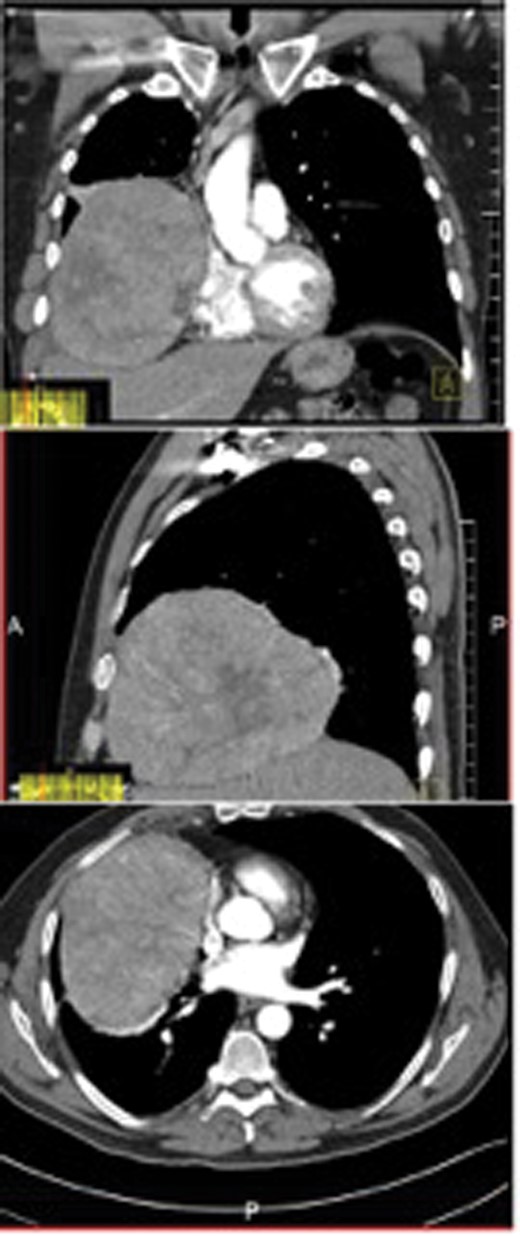

A chest X-ray showed elevation of the right hemidiaphragm, and therefore a computed tomography (CT) scan was performed, demonstrating a 15 cm right-sided lower intrapleural mass.

Coronal, sagittal and axial views of the CT scan showing a 15 cm intrapleural mass in the right lower chest cavity.